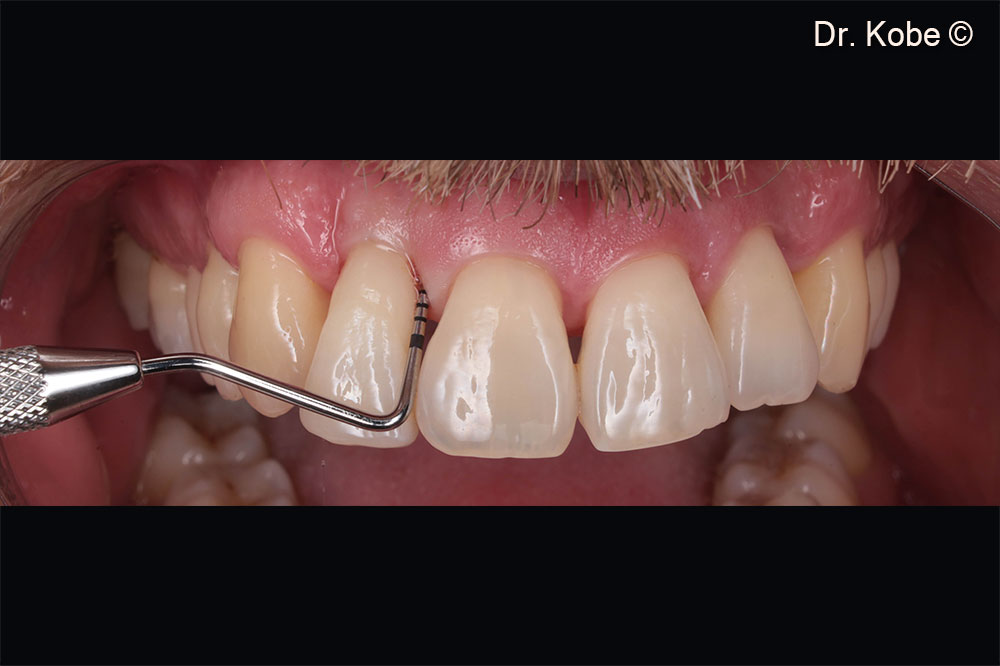

Vết thương lành hoàn toàn

Theo dõi một năm ở góc phần tư thứ nhất

Theo dõi một năm ở góc phần tư thứ hai